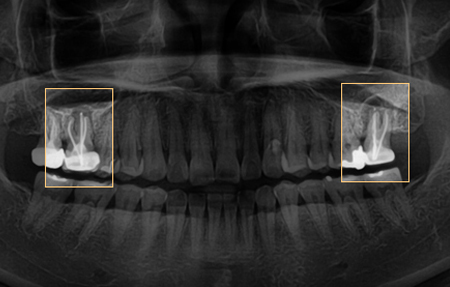

초진 방사선 사진

신경치료를 잘 했음에도 염증이 크게 생겼고 뿌리의 대부분을 염증이 차지하고 있어서 발치를 할 수밖에 없었습니다. 하지만 환자분께서 당분간 타지역에 가야해서 당장은 진행하기 어려운 상황이라고 하셨고, 발치는 타치과에서 진행하기로 했습니다. 본원에서는 환자분께 발치하면서 뼈이식을 함께 하시는게 좋고, 뼈이식이 필요한 이유를 설명드렸습니다. 이후 6개월 뒤 본원에 내원하셨습니다.

→ 타 병원에서 발치 후 6개월 뒤

검사해보니 사진 속 동그라미 안에 뼈가 부족했습니다. 여쭤보니 발치만 하고 뼈이식을 하지 못했다고 하셨습니다. 임플란트를 위해서는 임플란트 주변으로 뼈가 1.5mm 정도가 필요합니다. 지금은 임플란트를 심더라도 바깥쪽에 뼈 이식을 동반해야 하거나 안쪽으로 심게 되는데 그렇게 되면 나중에 보철을 올릴 때 방향이 좋지 않아 불편하게 됩니다.